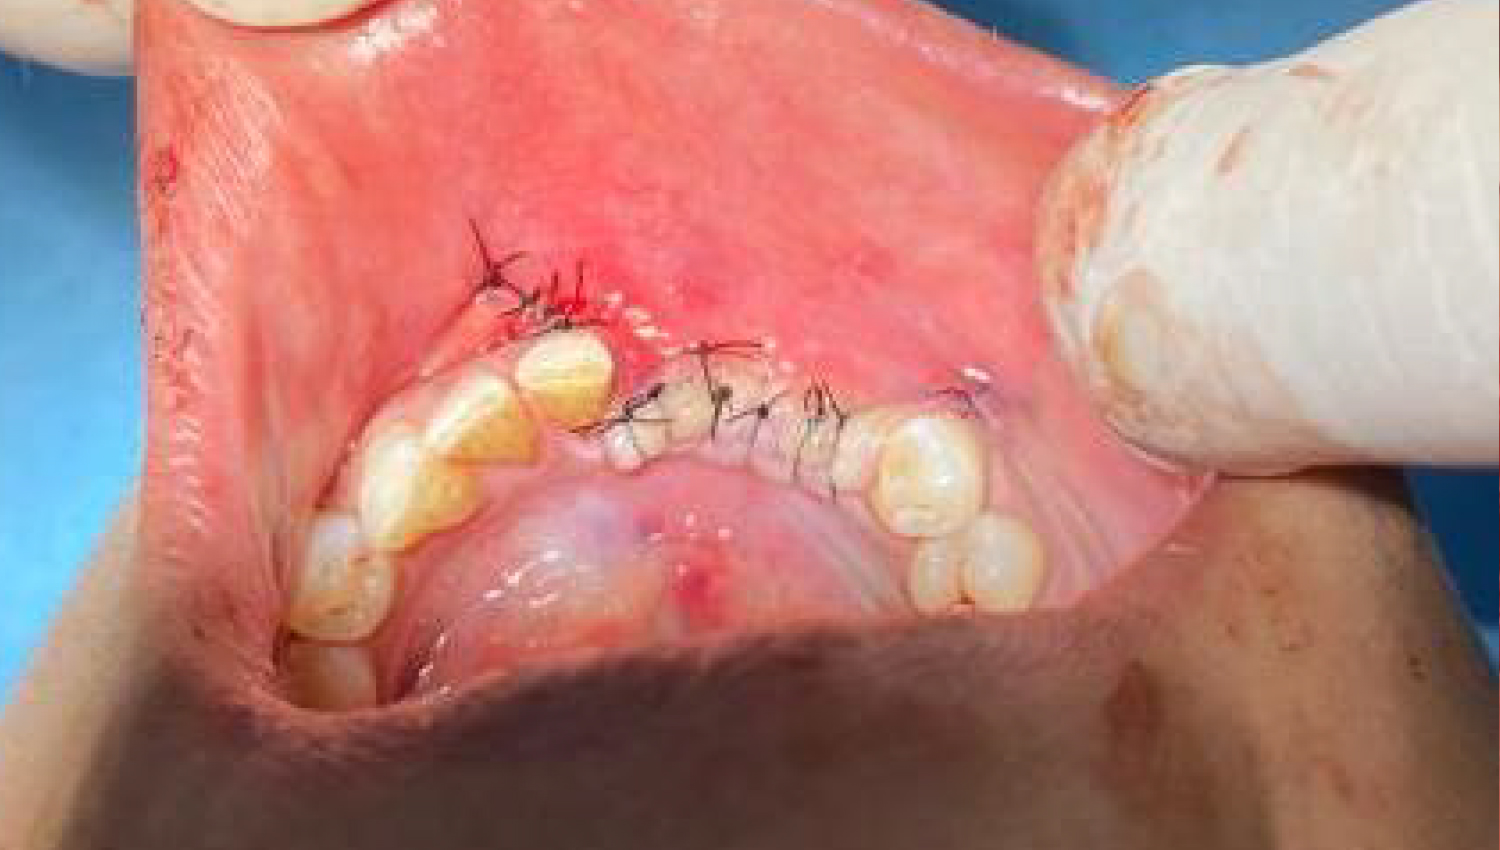

2.Initial clinical view.

5.The operation area was closed after the procedures.